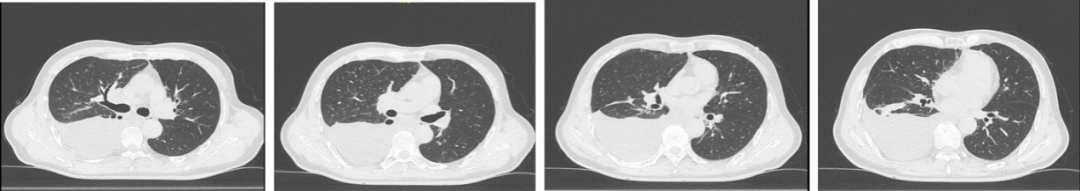

胸部CT检查:右肺下叶炎症、膨胀不全,右侧叶间胸膜结节状增厚,局限性肺气肿,纵隔淋巴结稍大,右侧胸膜转移、胸腔积液。

图1. 胸部CT显示右肺下叶炎症、纵隔淋巴结稍大,右侧胸膜转移、胸腔积液